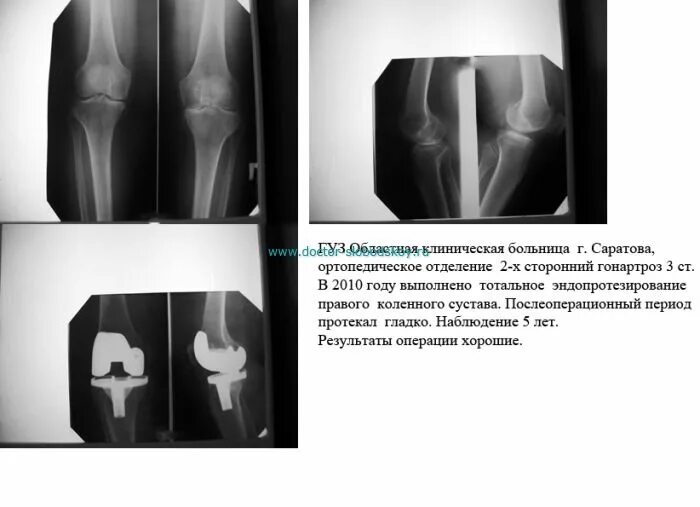

Гонартроз мрт